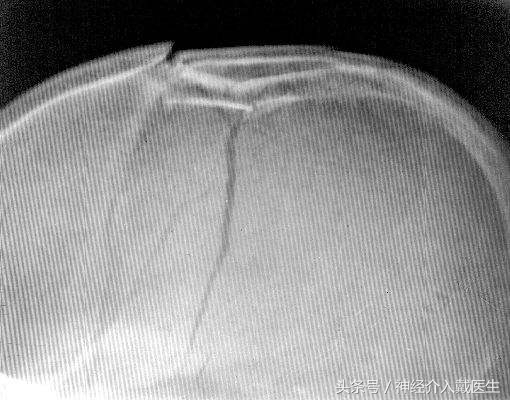

颅骨骨折的分类 按颅骨骨折的部位,可分为颅盖骨折及颅底骨折。根据骨折的形态不同,又可分为:线形骨折、凹陷骨折、粉碎骨折、洞形骨折及穿透性骨折。

此外,按骨折的性质,视骨折处是否与外界相通,又分为闭合性骨折及开放性骨折,后者包括颅底骨折伴有硬脑膜破裂而伴发外伤性气颅或脑脊液漏者。 单纯的线形骨折本身无需特殊处理 ,

其重要性在于因骨折而引起的脑损伤或颅内出血,尤其是硬膜外血肿,常因骨折线穿越脑膜中动脉而致出血。因此,凡有骨折线通过上矢状窦、横窦及脑膜血管沟时,皆应密切观察、及时作可行的辅助检查,以免贻误颅内血肿的诊断。 线形骨折常伴发局部骨膜下血肿,尤以儿童较多。当骨折线穿过颗肌或枕肌在颠骨或枕骨上的附着区时,可出现颞肌或枕肌肿胀而隆起,这一体征亦提示该处有骨折发生。